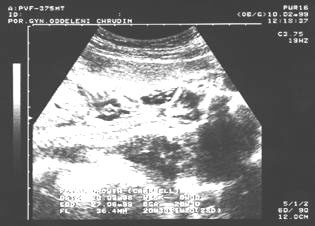

9. týden: plodové vejce

9.týden